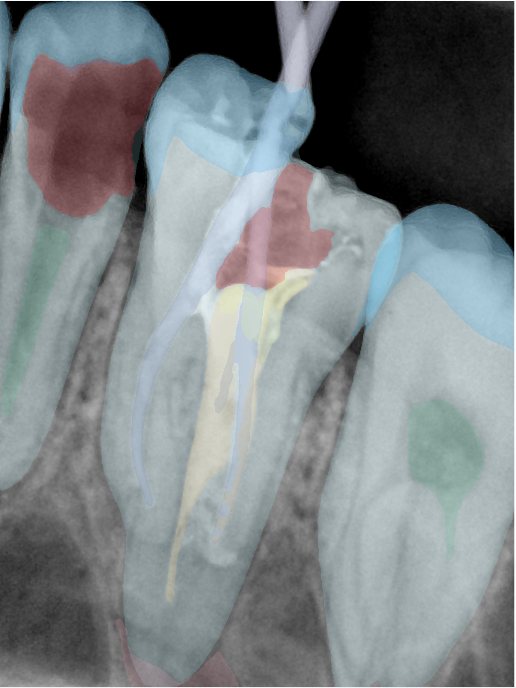

CR/DR 牙齿分割阶段记录

当前进展

- 完成了 CR/DR 牙齿相关分割训练

- 当前结果已经达到阶段预期,但仍有细节问题需要继续处理

相关测试

遇到的问题

- 训练过程中出现过 mask 下移问题

- 部分结果会出现 box 填充异常

- mask 边缘仍然有比较明显的锯齿感

参考

第二版算法问题测试

| 第一版 | 第二版 | 是否解决 | |

|---|---|---|---|

![]() | ![]() ![]() 边角识别有问题 龋齿识别不全 牙髓识别不全 | ![]() | 解决 |

![]() | ![]() 边角识别有问题 识别信息有误 自查(牙冠识别不全) | ![]() | 解决 |

![]() | ![]() ![]() 边角识别有误 大范围填充识别遗漏 | ![]() | 解决 |

![]() | ![]() 识别信息不全 | ![]() | 解决 |

![]() | ![]() ![]() 边角问题 牙胶识别不全 牙冠识别不全 | ![]() | 解决 |

![]() 换图片 | ![]() | ![]() 牙冠部分稍微白了一些就识别成小范围修补,部分判断异常 | 部分解决,修复类略敏感,牙冠部分稍微白了一些就识别成小范围修补,部分判断异常。 |

![]() | ![]() ![]() 牙冠识别不全 牙髓不全 根尖炎龋齿识别有误 | ![]() | 解决 |

![]() | ![]() | ![]() | 解决 |

![]() 换图片 | ![]() | ![]() | 解决 |

![]() | ![]() 牙冠识别有误 | ![]() | 解决 |

![]() 换图片 | ![]() ![]() 边角识别有误 | ![]() 修复类敏感 | 部分解决,图像过白,导致修复类判断异常。 |

![]() 换图片 | ![]() 牙冠识别不全 | ![]() 修复类敏感 | 部分解决,图像过白,导致修复类判断异常 |

结论:修复类出现了不鲁棒的情况,后续需要加入轮廓的扩充数据进行增强。